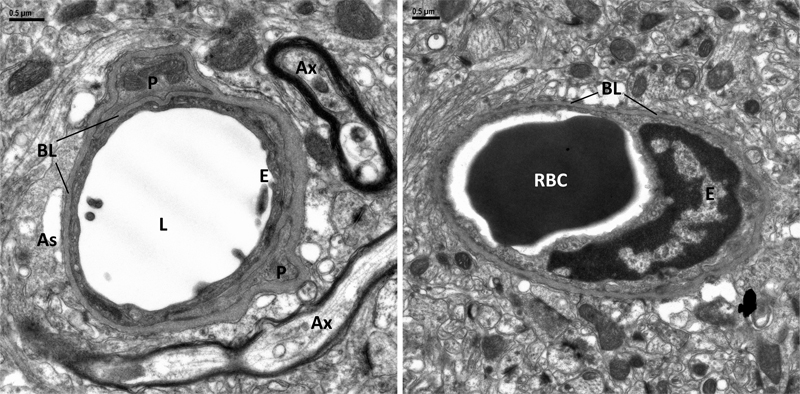

Introduction Capillaries are the smallest segment of the vascular network throughout the body and play crucial roles in exchange of oxygen, nutrients, pharmaceuticals, and waste between vascular and perivascular tissues [1]. Electron microscopic (EM) studies show capillary lumens are covered by a single layer of endothelial cells and the abluminal side is covered by a basal lamina (BL, basement membrane], which is formed by the fused BL of endothelial cells and pericapillary astrocytes [2–4]. Pericytes and their processes are present focally in the fused BL. Fig 1 illustrates the anatomical relationship between capillary lumen, endothelial cell, pericyte, pericapillary astrocyte, and basal lamina.

Fig 1. Electron micrograph of a capillary in cross section from the cortex of a 5.5-month-old non-Tg mouse. Perfusion of fixative cleared the lumen (L) that is lined with a thin layer of endothelial cells (E) abutting a homogenous basal lamina (BL), Pericapillary astrocytes (As) and their end-feet are tightly attached on the other side of the BL. Pericyte (P) and its processes are embedded in the BL. The sketch illustrates the anatomical relationship between vascular cells and BL. In the central nervous system (CNS), capillary endothelial cells have specific structures that control movements of molecules between the blood and brain parenchyma to maintain homeostasis of the CNS [5], as well as regulation of blood flow [6]. These structures include interendothelial tight junctions, luminal and abluminal molecular transporters, and a paucity of vesicular transport, which constitutes the blood-brain-barrier (BBB). Pericytes are also involved in BBB function and blood flow [7, 8]. EM of well-preserved/fixed mouse and rat CNS has made this ultrastructural definition of the capillary BBB universally accepted in other animal species. The non-cellular capillary structure, BL, sandwiched between the abluminal side of endothelial cells and pericapillary glial cells, also plays a key role in barrier functions and immune response in the CNS [9–11]. Early biochemical studies of BL from non-CNS tissues of human and mouse have identified major and minor components and their molecular interactions [12]. Non-fibrillar collagen type IV [Col 4] is biochemically the most abundant component of BL. Col 4 interconnects with non-collagenous components, including laminin, perlecan, nidogen and fibronectin, to form an amorphous meshwork with a homogeneous density on EM. These biochemical data, like morphological data, are also accepted universally. The Col 4-dominant biochemical view also prevails in CNS capillary BL. Compared to Col 4, other BL components are understudied [13]. Early studies in rats have shown that BL could be a physical barrier to certain intravenously injected molecules after they pass the BBB [14, 15]. It is hypothesized that electric charges of BL components contribute to barrier function. Investigators have tried to translate data from mouse models of human disease to clinical trials in humans; however, such translational studies have often not succeeded. The difference between human and mouse capillaries may contribute to this finding. Intravenously administered molecules that can bypass BBB have some success treating mouse models of human neurodegenerative diseases but have minimal effect in humans for currently unknown reasons, and the role of vascular cells and BL needs to be considered. Recent studies have shown differences in brain cells and microvascular cells between humans and mice. Significant differences in expression were found in specific brain regions [16–20]. Similar studies have not been performed in human and mouse spinal cords. The differences in expression in cell types between species could produce different BL properties in human and mouse CNS, which might interfere with the movement of molecules/drugs within the perivascular compartment. Fifty years ago, Cervós-Navarro and Ferszt [21, 22] described ultrastructural characteristics of capillaries in human spinal cords of individuals ranging in age from 7-months to 97 years. They found a consistent “dilated pericapillary space” bordered on one side by endothelial BL and on the other side by perivascular glial cells, with collagen fibers in about 70 % of the capillaries. In 1998, Ono et al. [23] studied spinal cord capillaries in patients ranging in age from 37 to 74 years with sporadic amyotrophic lateral sclerosis (sALS), other neurologic diseases and in neurologically normal controls. They found that about 40 % of capillaries in the three groups had a “focally split BL to encompass a large area containing accumulation of collagen fibrils.” In 2012, Garbuzova-Davis et al. [24] described expanded capillary BL with collagen fibrils in spinal cords of 18 controls [39–86 years] and in sporadic ALS [45–83 years]. In 2013, we showed similar findings in a preliminary report of 8 controls (28–81 years), 5 sALS (47–75 years) and 7 familial ALS (15–69 years) patients [25]. In 2015, Sasaki [26] examined 358 and 366 capillaries in 12 controls (50–80 years) and 12 sALS (59–83 years) cases and found “slight or abundant accumulation of collagen fibers in the perivascular space within expansion of the capillary basement membrane” in controls and ALS cases. Expanded spaces in BL of spinal cord capillaries have not been reported in normal mice or ALS mouse models. In contrast to spinal cord capillaries, early EM studies of human cerebral capillaries only briefly comment on collagen fibrils in BL, with a few images: 61-year-old [27], age unknown [28], fetus [29, 30], 50–66 years [31], 56 years [32] and age unknown [33]. Splitting of the BL has also been observed in capillaries of biopsy tissues from patients with cerebral edema (58–80 years) [34], multiple sclerosis (25–30 years) and Alzheimer’s disease (AD) (age unknown) [35, 36]. Later, Farkas et al [37] examined human cerebral periventricular white matter and showed collagen fibrils within capillary BL in patients 40 to 90 years of age. They also reported increased BL pathology in AD and Parkinson’s disease. Szpak et al [38] showed cerebral capillaries with numerous collagen fibers in two AD patients (36–46 years) with a p.P117L PSEN1 mutation. They all showed banded collagen fibrils with EM. In a preliminary EM report of human brain capillary BL (11 cases, 7–49 years of age), we showed banded collagen in expanded spaces in the basal lamina [39]. Some studies have reported collagen types other than Col 4 in human brain capillaries. van Duinen et al [40] showed immunohistochemical (IHC) staining of collagen type I (Col 1) and collagen type III (Col 3) and fibronectin in capillaries of normal controls aged 36–78 years. Dong et al [41] studied six patients (46–83 years old) with cerebral autosomal dominant arteriopathy with subcortical infarcts and leukoencephalopathy with NOTCH 3 mutations (CADASIL) and six controls (54–82 years old). They found Col 1 and Col 3 in capillaries of both CADASIL and control cases. Staining was heterogeneous with much lower frequency and intensity in controls. In our preliminary EM reports of human CNS capillary BL, IEM localized Col 1 and Col 3 to fibrillar collagens in the expanded spaces [25, 39]. IHC and proteomic analysis showed Col 6α3 in controls, AD and cerebral amyloid angiopathy (CAA) and Col 6ɑ2 in individuals with CAA ranging in age from 65–95 years [42], and Col 1ɑ1 in AD with CAA ranging in age from 58–97 years [43], and in all vessels of CAA cases ranging from 61–83 years old [44]. The sparse EM studies of CNS capillary BL in young human cases prompted our studied of capillary BL with IHC, EM and IEM in cases ranging in age from 4 days to 49 years. The cases had no significant brain pathology or a range of neurological disorders. We limited the study to those 50 years of age or younger to minimize the possible effects of age-related neurodegenerative or cerebrovascular changes [45, 46]. Additionally, considering the increased attention on species differences between brain vasculature of humans and mice [19, 20, 47], we included normal and transgenic (Tg) mouse models of human neurodegenerative diseases. Material and Methods Brains and spinal cords Table 1 listed human brains and spinal cords from the brain bank in Mayo Clinic, Jacksonville, FL. A total of 45 cases aged from 4 days to 49 years old that included 18 cases with no significant brain pathology and 27 cases with different neurological disorders. Among them were two biopsies and 10 cases with postmortem interval (PMI) of less than 24 hours. Neuropathologic assessments were based on light microscopic examination of paraffin sections. Table 2 CNS tissues were from non-Tg and Tg mice developed in Mayo Clinic, Jacksonville, FL [48–50].

Fig 25. 5.5-months-old non-transgenic mouse (equivalent to 30-years-old human). Cortex. Two capillaries both have a fused basal lamina (BL) of endothelial cell (E), pericyte (P) and perivascular astrocyte (As). Note the homogeneity and uniform thickness of amorphous BL. RBC, red blood cell in the lumen (L); Ax, myelinated axon.

Fig 26. 5.5-month-old non-transgenic mouse (equivalent to 30-years-old human). Spinal cord. Top. Longitudinal section of a capillary showing fused basal lamina (BL) of endothelial cell (E), pericyte (P) and perivascular astrocyte (As). Bottom. Enlarged box areas. Note the homogeneity and uniform thickness of amorphous BL. L, capillary lumen; Ax, myelinated axon.